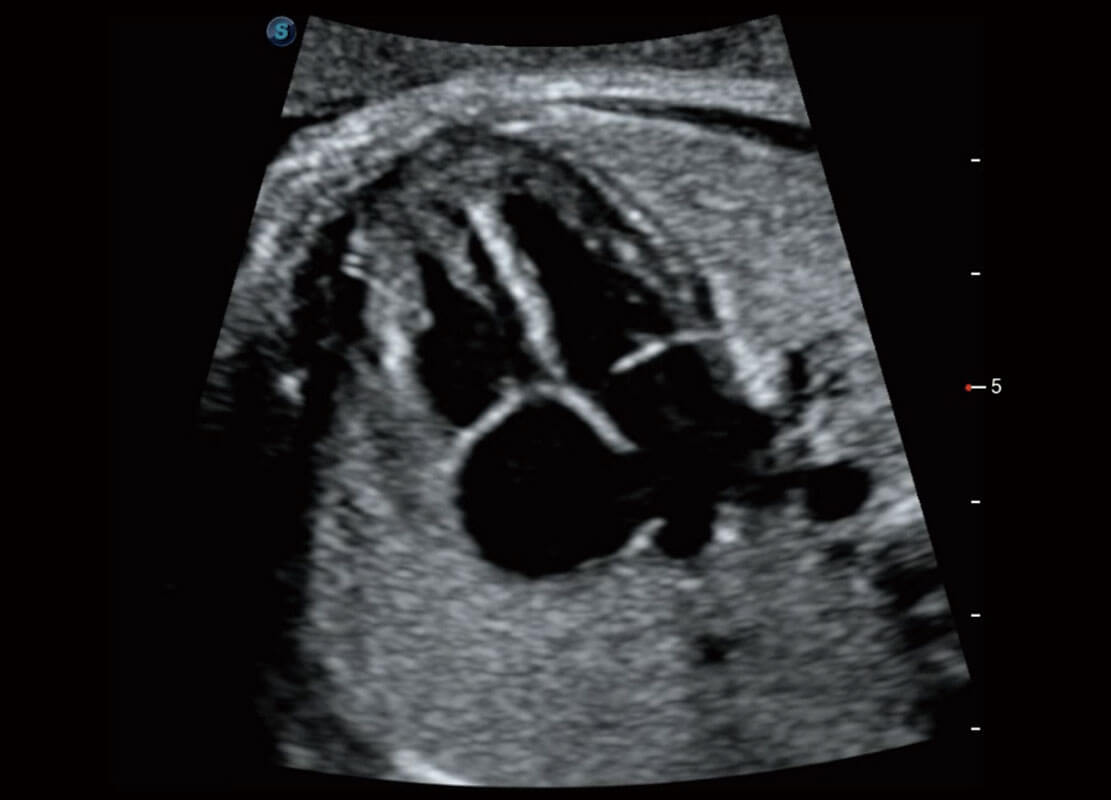

P60搭载一系列胎儿心脏成像技术,实现精细的胎儿心脏评估。

四腔心血流

右室双出口